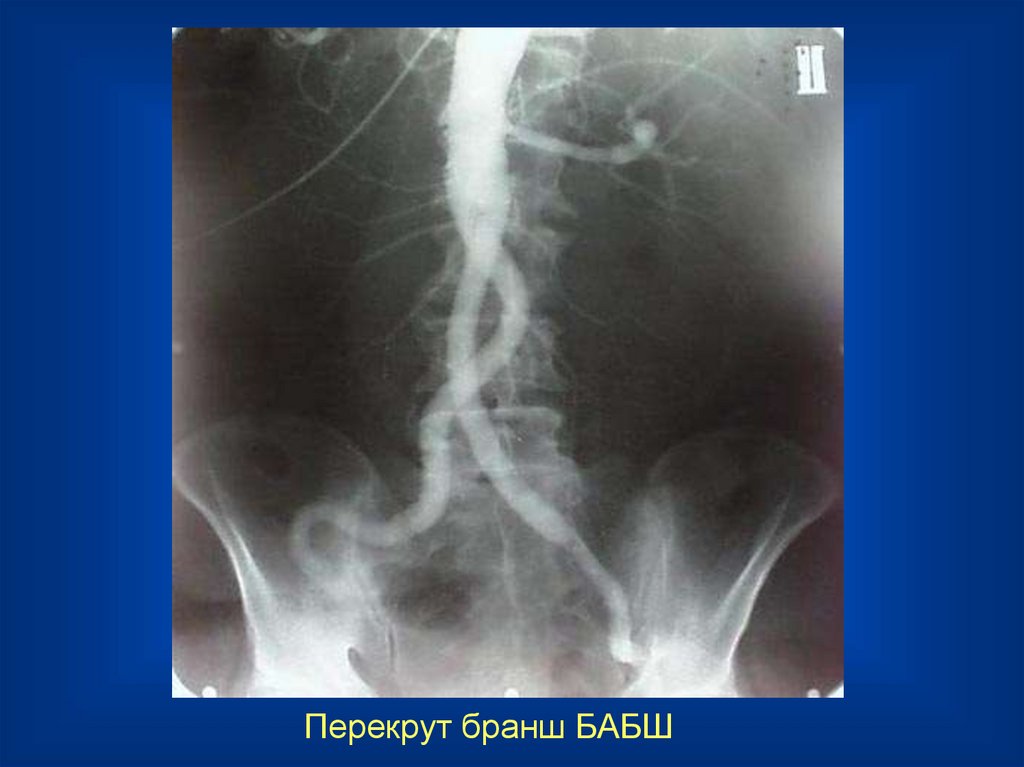

Перекрут бранш БАБШ